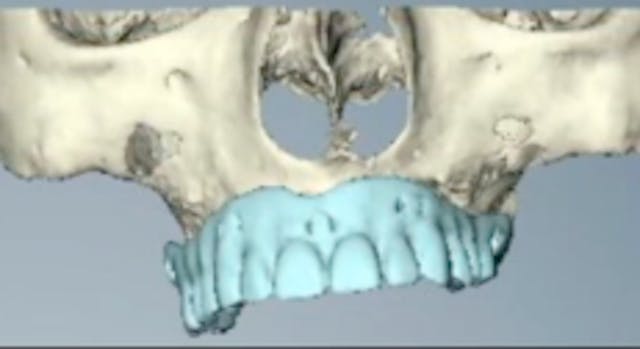

CAT# CV-046

Zygomatic Implants - Treatment Plan

Dr. Francesco Mintrone